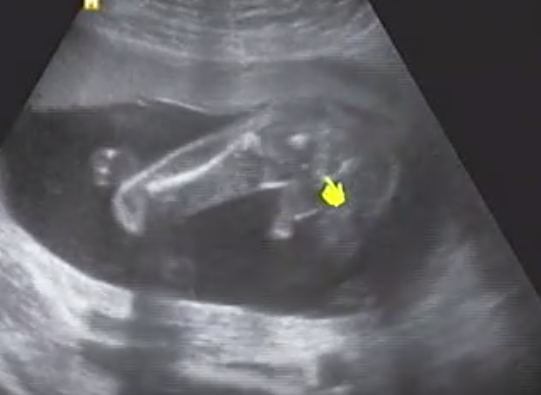

둘째를 임신하고 눈곱만큼도 아기의 성별이 궁금하지 않았습니다. 하지만... 정기검진을 갔을 때 그때가 임신 10주가 막 지났을 무렵이었는데, 의사선생님께서(첫째도 받아주시고, 딸을 많이 원한다는 걸 잘 알고 계시는 선생님) 묻지도 않았는데 다리 사이에 뭐가 반짝이는 거 같다며, 더 지나봐야 확실하겠지만 자꾸 다리 사이에 반짝이는 게 마음에 걸린다며, 아들일 것 같다고 하셨습니다.

그날 집에 가서 초음파 영상을 몇 번을 돌려봤는지 모릅니다. 아무리 돌려봐도 모르겠어서 빛나는 것은 탯줄이리라 생각하고 다음 검진을 초조하게 기다렸습니다.